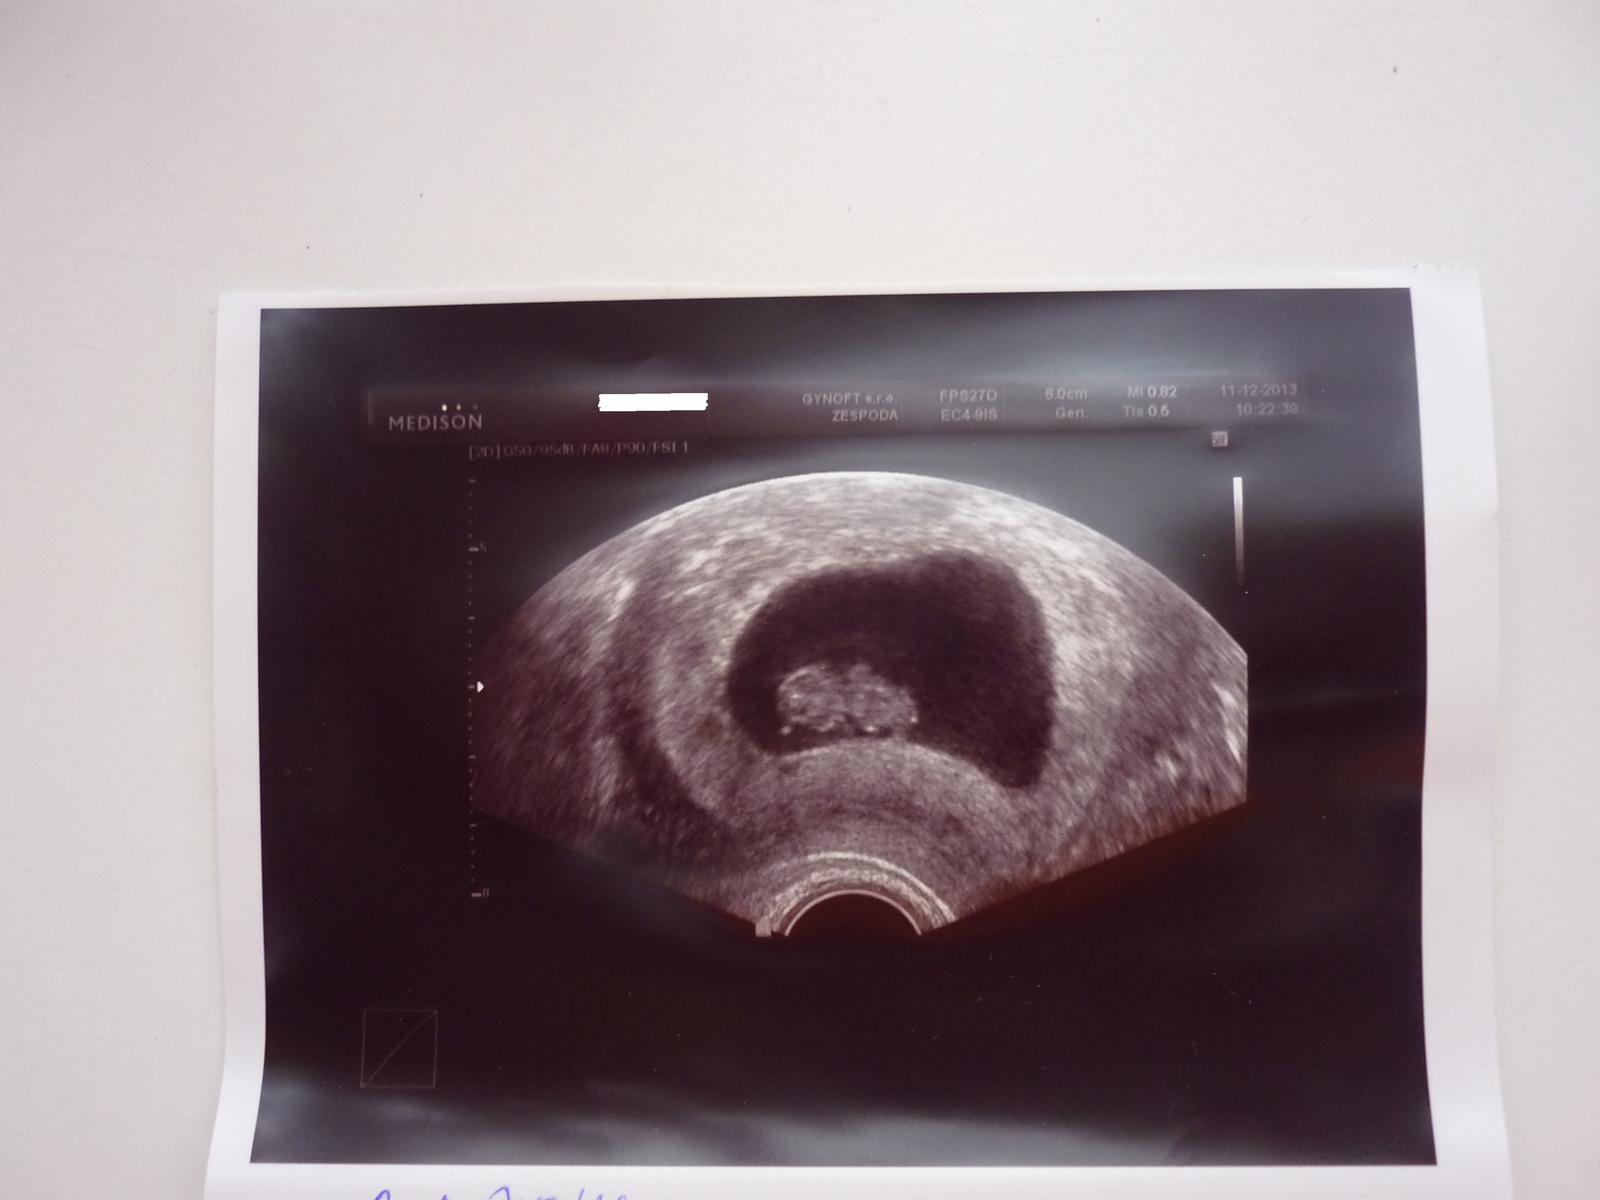

@petulaho Petulko mám moc velkou radost. Fotečka je úžasná i fakt dobře viditelná, asi moc dobrej přístroj a dobrý sonografista a hlavně ideální model či modelka🙂

@petulaho Krásná fotečka, jsem moc ráda, že tak pěkně rostete. Opatruj se a ať je Ti brzy lépe. 🙂